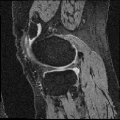

We applied AutoReg to a wide range of MRI registration scenarios from mono-modality (registering brain T1 images to an averaged T1 template, brain T1 to T1 images, brain T2 to T2 images, knee T1 to T1 images, and lung CT inspiration to expiration images) to multi-modality (registering brain T1 to T2 images, brain T2 to T1 images).

Knee T1-to-T1 registration. We employ knee MRIs from the Osteoarthritis Initiative 444https://nda.nih.gov/oai/ with corresponding segmentations of femur and tibia as well as femoral and tibial cartilage [49]. We divide images into 377, 21 and 130 volumes for training, validation and testing. All images are resampled to isotropic spacing of 1mm, in size of .

Table. IX demonstrates performance in terms of Dice score on challenging registration tasks, including brain T1 MR image-to-image, brain T2 MR image-to-image, multi-modal (including T1-to-T2 and T2-to-T1), and knee T1 MR image-to-image registrations. While our method gives an obvious lower variance with a comparable Dice for all of these cases. Fig. 6 depicts the stability of the methods in view of the box-plot of Dice score, where fewer outliers and lower variance indicate a more stable registration. Note that, the optimization-based methods perform slightly better for the brain registration where the image pairs are much more similar to each other. However, they are less satisfying in the knee T1-to-T1 registration. When faced with such various challenging cases, learning-based models struggle to provide comprehensive solutions. While our method gives an obvious lower variance with a comparable mean of Dice for all these cases, showing stronger stability.

Our representative registration results are given in Fig. 7 and Fig. 8. The first three registration cases in Fig. 7 contain image-to-atlas on T1 brain MR, image-to-image on T1 brain MR and T2 brain MR test pairs. The large deformations in scans make registration challenging and difficult. As a result, all the source images are well aligned to the target. The second three rows in Fig. 8 contain knee T1 MR data, multi-modal data, and lung CT inspiration-expiration images. Although large deformations and intensity differences exist in scans, source images are well aligned to the target, demonstrating our outstanding performance.